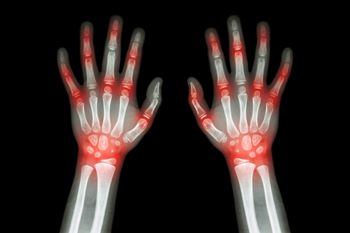

Rheumatoid Arthritis